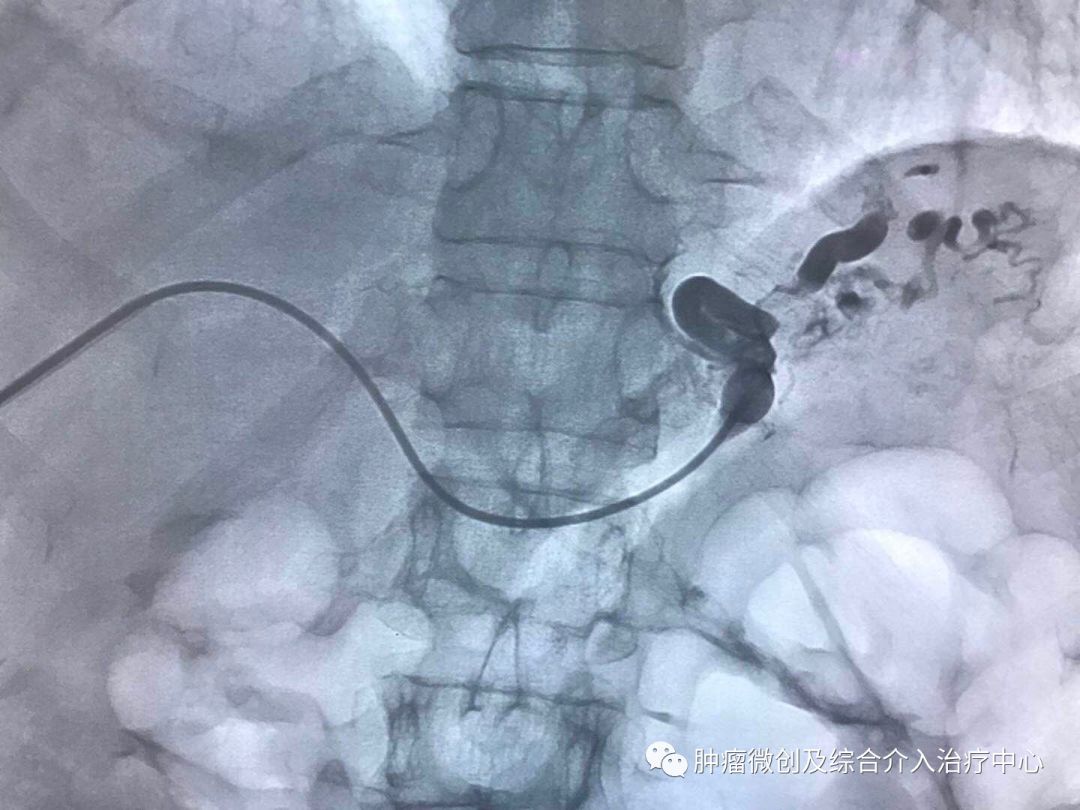

(介入栓塞术后提示无肾动脉出血肾动脉-栓塞成功)

运城第一医院肿瘤介入科专家,运城市第一医院介入科专家